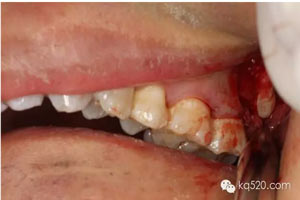

圖1.術前口內(nèi)像:上頜結節(jié)后份有一溢膿的瘺道,看不到28。